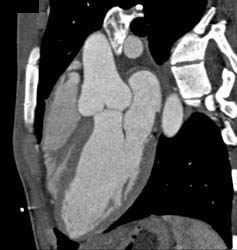

LAD Plaque in Multiple Images and Projections